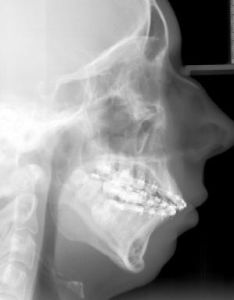

在半側顏面短小畸形的臨床表現中,可累及多個解剖部位且嚴重程度不一,表現為患側面部短小,皮下軟組織薄弱,頦部偏斜,面神經發育不良,面橫裂及外耳畸形等,其中以骨骼畸形以下頜骨發育不良最常見也最重要,嚴重者可累及上頜骨、顴骨、顴弓及顱顳部骨骼,其中下頜骨的畸形是最明顯,而且下頜骨受累的嚴重程度與面部其他部位包括眶部、顴骨、外耳、軟組織的受累程度呈正相關,具體詳述如下:

其他顱面骨骼受累與下頜骨的嚴重程度有關,患側上頜骨的垂直高度縮短,咬牙合平面相應向患側向上傾斜,患側上頜恆磨牙萌出延遲,嚴重者伴有顴骨發育不良,顴弓窄小,甚至缺失,顴部的發育不良與下頜骨髁狀突及升支畸形有直接相關性。乳突可有發育不良,乳突房的氣化程度不一。莖突縮短或缺失。眼眶在各個方向的發育不良不常見,部分患者伴有小眼。患側額骨可表現為平坦,類似於斜頭畸形的表現,但無單側冠狀縫早閉。頸椎畸形包括偏側脊椎發育不全、畸形融合,腦幹扁平。

第一二鰓弓綜合徵此外,下頜骨的畸形會導致上頜骨及其他顱面骨的繼發發育異常,患側咬頜平面向上傾斜,上頜骨的向下生長受限,阻礙了眼眶與上齒槽嵴和鼻梨狀孔區正常的進行性分離,致眶底與上頜牙槽弓的垂直距離縮短,嚴重者伴顴骨發育不全,顴弓的跨距縮短,導致患側外眥與耳屏水平連線距離縮短,所以可以說,下頜骨畸形是半側顏面短小畸形的基石,故矯治下頜骨的畸形也成為治療的關鍵。

患者出生後,畸形是否會呈進行性發展,這也關係到治療時機的選擇。大部分的研究表明,半側顏面短小畸形會隨生長發育有所加重,表現為梨狀孔平面進行性的傾斜,患側下頜角的位置較對側上移,這種進行性加重的程度與下頜骨本身畸形的嚴重程度有關。大部分患者出生時僅有下頜骨的畸形,其咬牙合平面、梨狀孔及眼眶均無明顯的傾斜及不對稱,但隨著雙側的不對稱發育,面部的不對稱呈漸進性加重。兒童時期用肋軟骨重建下頜骨升支及髁狀突後,如重建的升支與對側能同步發育,且開牙合處有牙齒萌出,其咬牙合平面及雙下頜角間的連線不傾斜,但如重建升支沒有與對側同步發育時,其咬牙合平面、雙下頜角間的連線及梨狀孔漸進性傾斜。甚至在早期進行了下頜骨延長術的患者,延長後的下頜骨其生長速度仍不及正常側,隨生長發育也可表現出不同程度的下頜骨升支不對稱及咬牙合平面的傾斜。